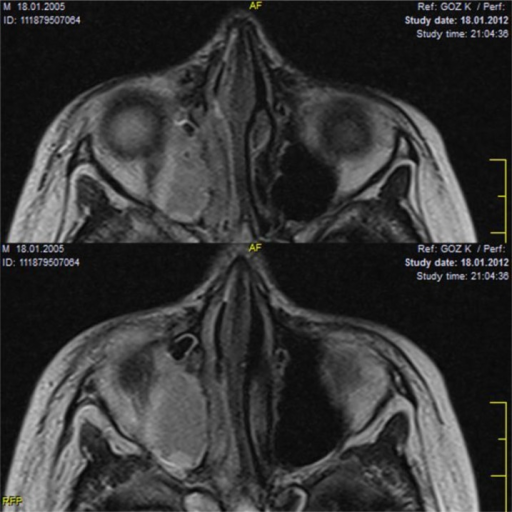

| III | 골막하 농양 | CT에서 골막하 농양 확인 |

| IV | 안와 농양 | 안와 내 농양 형성 |

- CT (안와+부비동): 필수 — 농양, 부비동염 확인